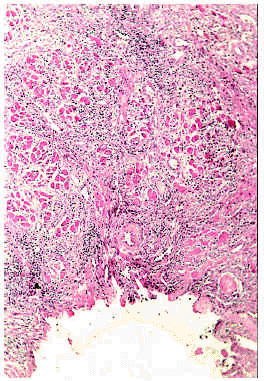

Desde el punto de vista histopatológico, en las etapas iniciales se observa espongiosis en la pared del infundíbulo folicular a expensas de un infiltrado de eosinófilos y células mononucleares. En etapas avanzadas del proceso se puede apreciar un auténtico clivaje o vesícula longitudinal, con neutrófilos, linfocitos y gran número de eosinófilos, que separa toda la pared infundibular (fig. 3) y afecta, con frecuencia, a la glándula sebácea (fig. 4)21. Algunas pústulas, primariamente intrafoliculares, se extienden secundariamente desde el infundíbulo hacia la epidermis vecina formando pústulas epidérmicas subcórneas10. Es posible encontrar, además, algún grado de degeneración mucinosa de la vaina epitelial externa22, 23.

Fig. 3.--Foliculitis pustulosa eosinofílica: absceso infundibular.

Fig. 4.--Foliculitis pustulosa eosinofílica: infiltración eosinofílica de la glándula sebácea.